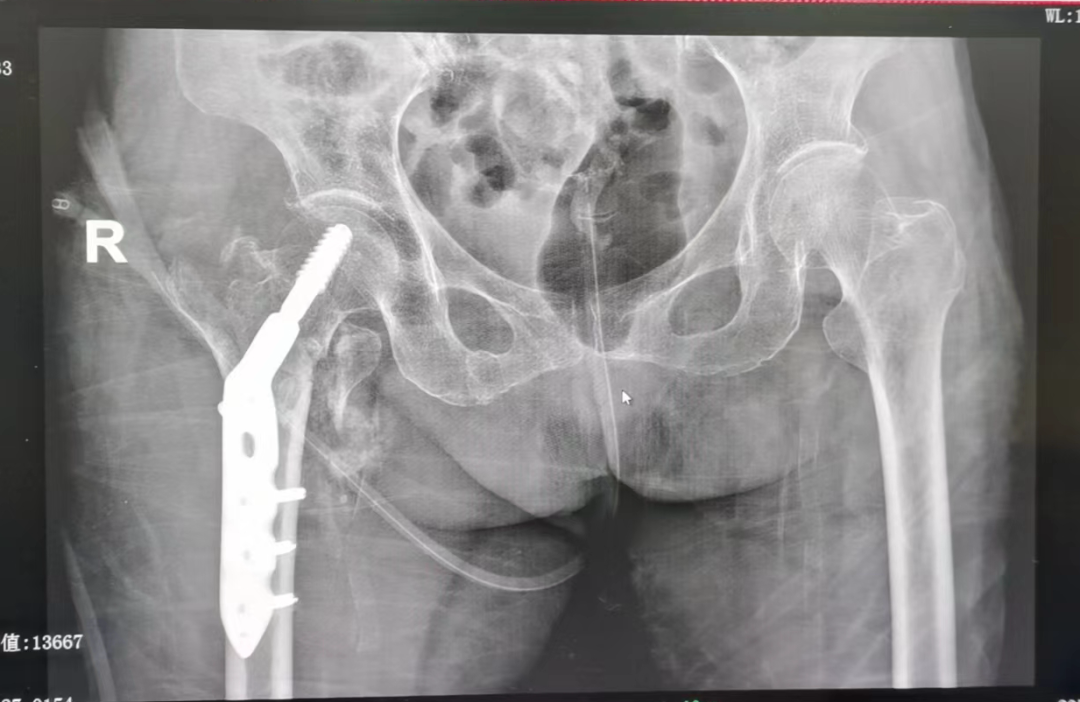

今年六月份,100岁高龄的周奶奶,在家中意外摔倒,下肢不能活动,在家卧床休息了九天,未有缓解,疼痛持续加重,家人送往我院外一科治疗。完善相关检查后确诊为右股骨粗隆间粉碎骨折。

(右股骨粗隆间粉碎骨折)

入院查体后发现,患者合并有骨质疏松症、冠心病、低蛋白血症,贫血、肺炎等严重基础疾病,如果保守治疗卧床时间很长,且无法护理,并发症多,风险大,死亡率高!